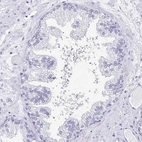

Immunohistochemistry analysis in human fallopian tube and prostate tissues using Anti-TCTEX1D4 antibody. Corresponding TCTEX1D4 RNA-seq data are presented for the same tissues.